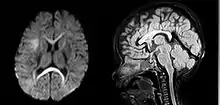

| An MRI of a patient with benign familial macrocephaly (male with head circumference > 60cm) | |